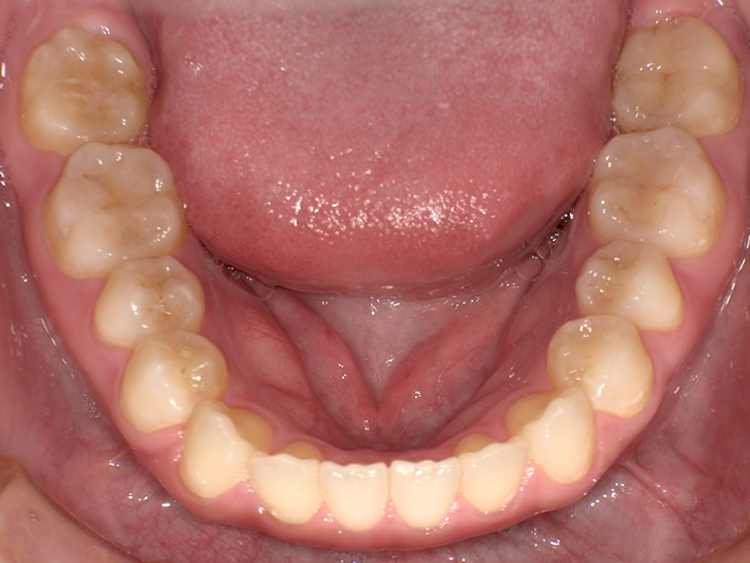

症例3

Before

After

| 主訴 | 上下の歯のガタガタを治したい |

|---|---|

| 年齢 | --- |

| 治療期間 | 約10ヶ月 |

| 治療内容 | インビザラインiGoで上下顎の治療。 狭まっていた歯並びを広げることで、 ガタガタに並んでいた歯を綺麗に並べた。 |

| 治療費 | ¥517,000(税込)+月額調整料 |

| 治療のリスク | 歯と歯の間を削ることでスペースを確保するので、 場合によっては歯が染みる症状が出ることがある。 |